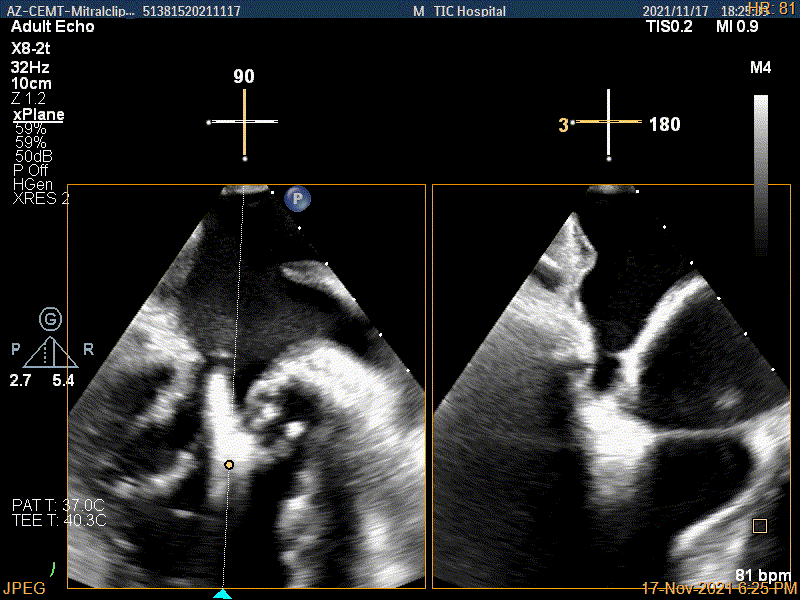

3D视图下进第二个夹子并建立trajectory

将第二个夹子置于第一个夹子内侧尽量靠近,并调节Rotate呈尽量平行关系

成功抓捕内侧残余脱垂区域瓣叶

第二个夹子夹闭后,反流量明显减少

3D视图两个夹子近似并排排列

3D-color视图下两个夹子间少量残余反流

肺静脉血流频谱恢复正向

二尖瓣瓣口平均跨瓣压差:3mmHg